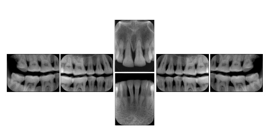

Intra-oral radiography typically involves acquisition of multiple images of various parts of the dentition. Many digital radiographic systems offer customized templates that are used for displaying the images in a study on the screen. These templates may also be referred to as mounts or view sets. The Structured Display Object represents a standard method of encoding and exchanging the layout and intended display of Structured Displays. A structured display object created in this manner could be stored with a study and exchanged with images to allow for complete reproduction of the original exam.

In most standard cases, images are oriented in structured layouts. These structured displays are useful to be shared between providers for reference purposes.